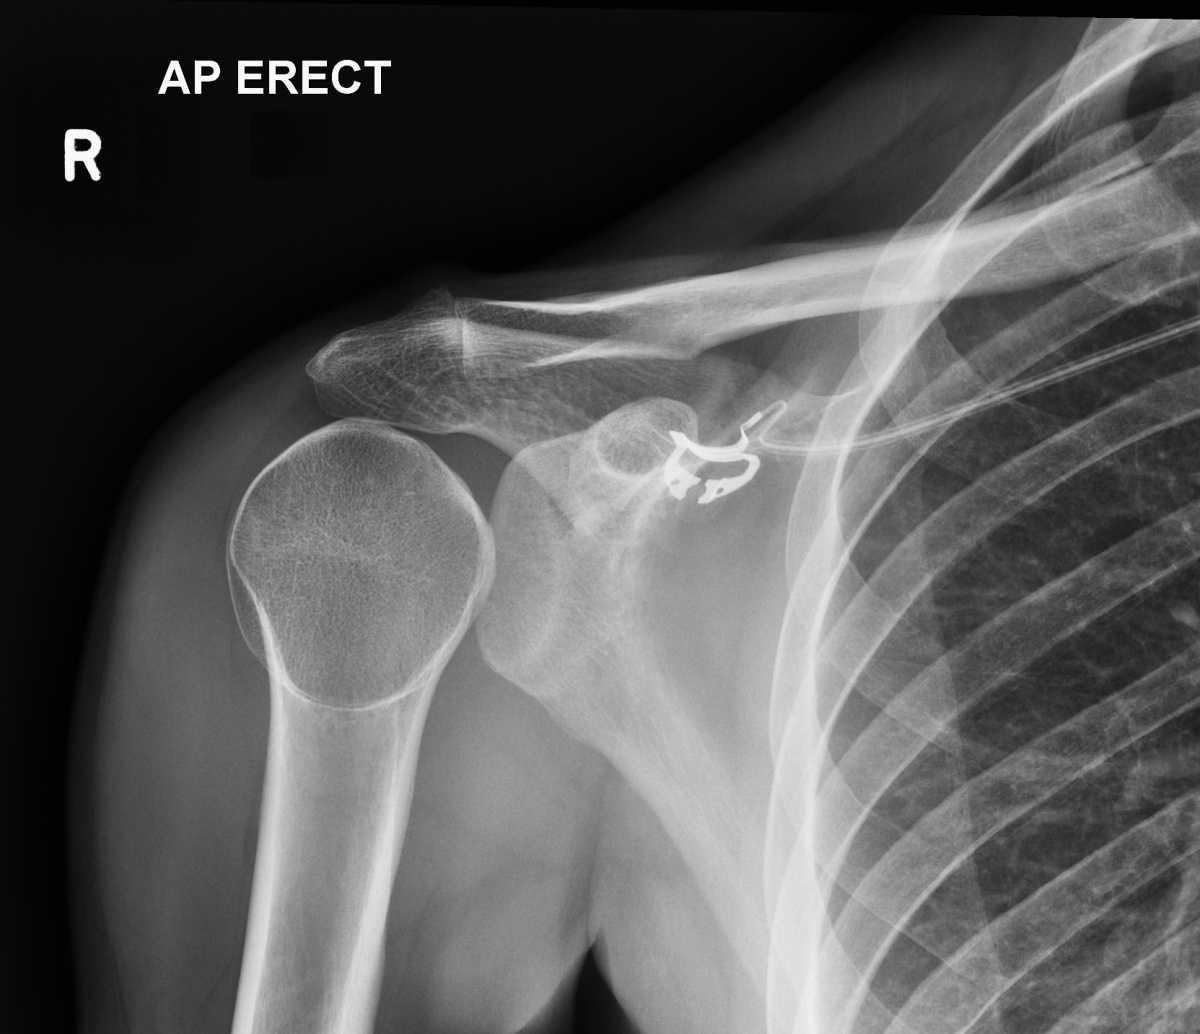

Luxation postérieure:

Y penser chez l’épileptique et en cas d’électrocution.

Aspect radiologique PIEGEUX:

- disparition de l’interligne articulaire (trop bel aspect sphérique de la tête humérale)

- cliniquement : rotation externe impossible (signe de l’aumône)

Andrew Murphy, Radiopaedia.org. From the case rID: 46646

Au moindre doute : cliché de Bloom et Obata (= profil axillaire traumatologique)